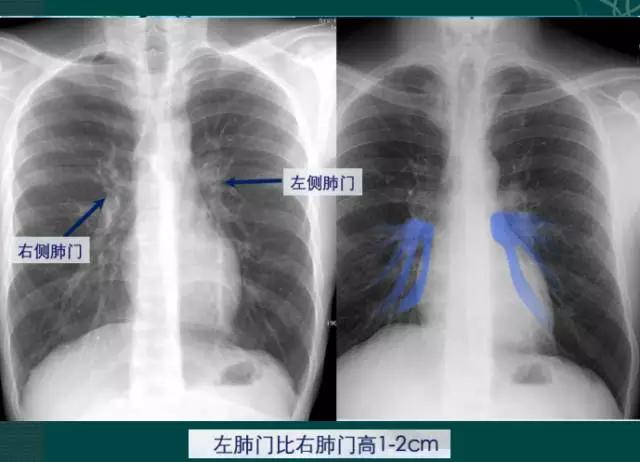

4、肺门的大小和位置

x线肺门指肺动脉、肺叶动脉、肺段动脉、伴行支气管以及肺静脉构成。

右肺门可分为上、下两部。上部约占1/3,由上肺静脉、上肺动脉及下肺动脉后回归支构成。上肺静脉下后干构成右上肺门的外缘;右肺门下部 约占2/3,由右下肺动脉干构成,其正常宽度不超过15mm,沿中间段支气管外缘平行向外下走行。右肺门上、下部相交形成一钝的夹角,称肺门角,正常该角顶清晰。如下图

左肺门亦分为上、下两部。上部由左肺动脉及其分支、左上叶支气管和左上肺静脉及其分支构成;下部由左下肺动脉及其分支构成,常被心影所遮盖。